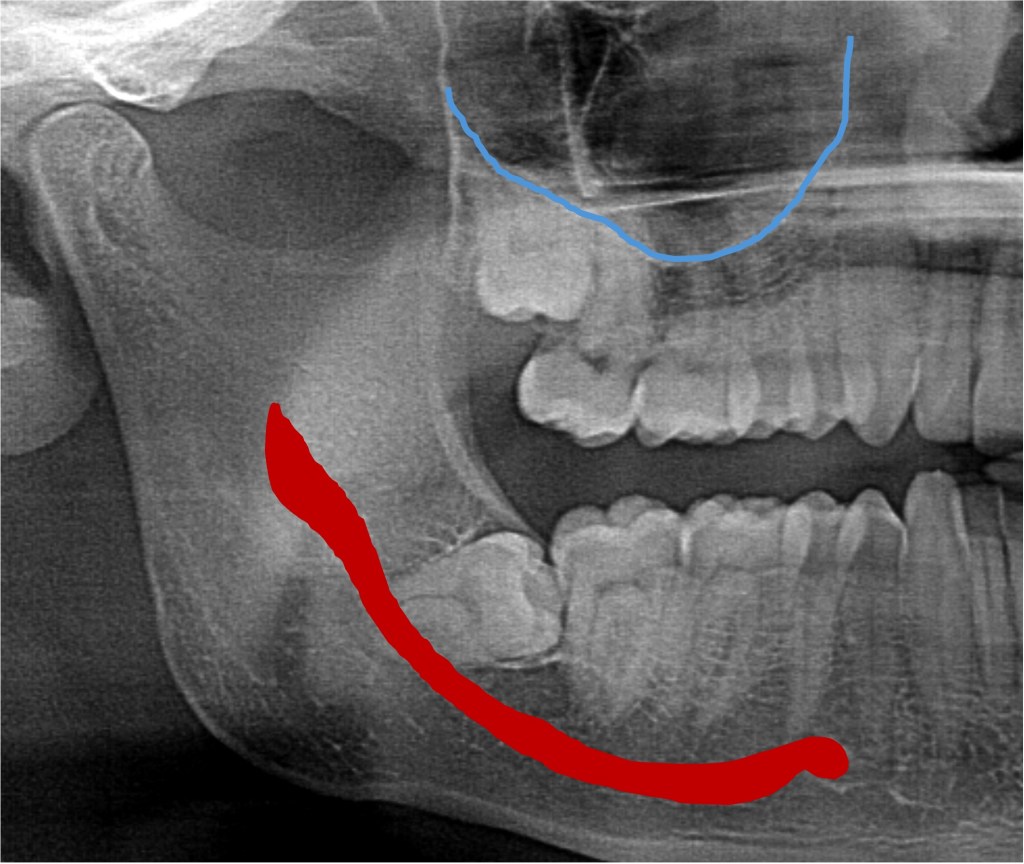

The force that pushes a tooth into the mouth is the formation of the root, which acts like a rocket to propel it, ideally, into the perfect position. The crazy thing is, the longer the roots get, the closer they get to important structures like the sinuses (near top wisdom teeth) and a nerve that gives the feeling to your lower lip and chin (bottom ones). If those roots get super close, touch, or “wrap around” those structures, there is increased risk of damage.

Fortunately injuries to these things are rare, but when they happen, they can be a problem. Here’s what we see on basic x-rays: